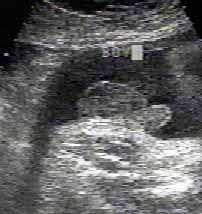

ولد في الاسبوع ال16